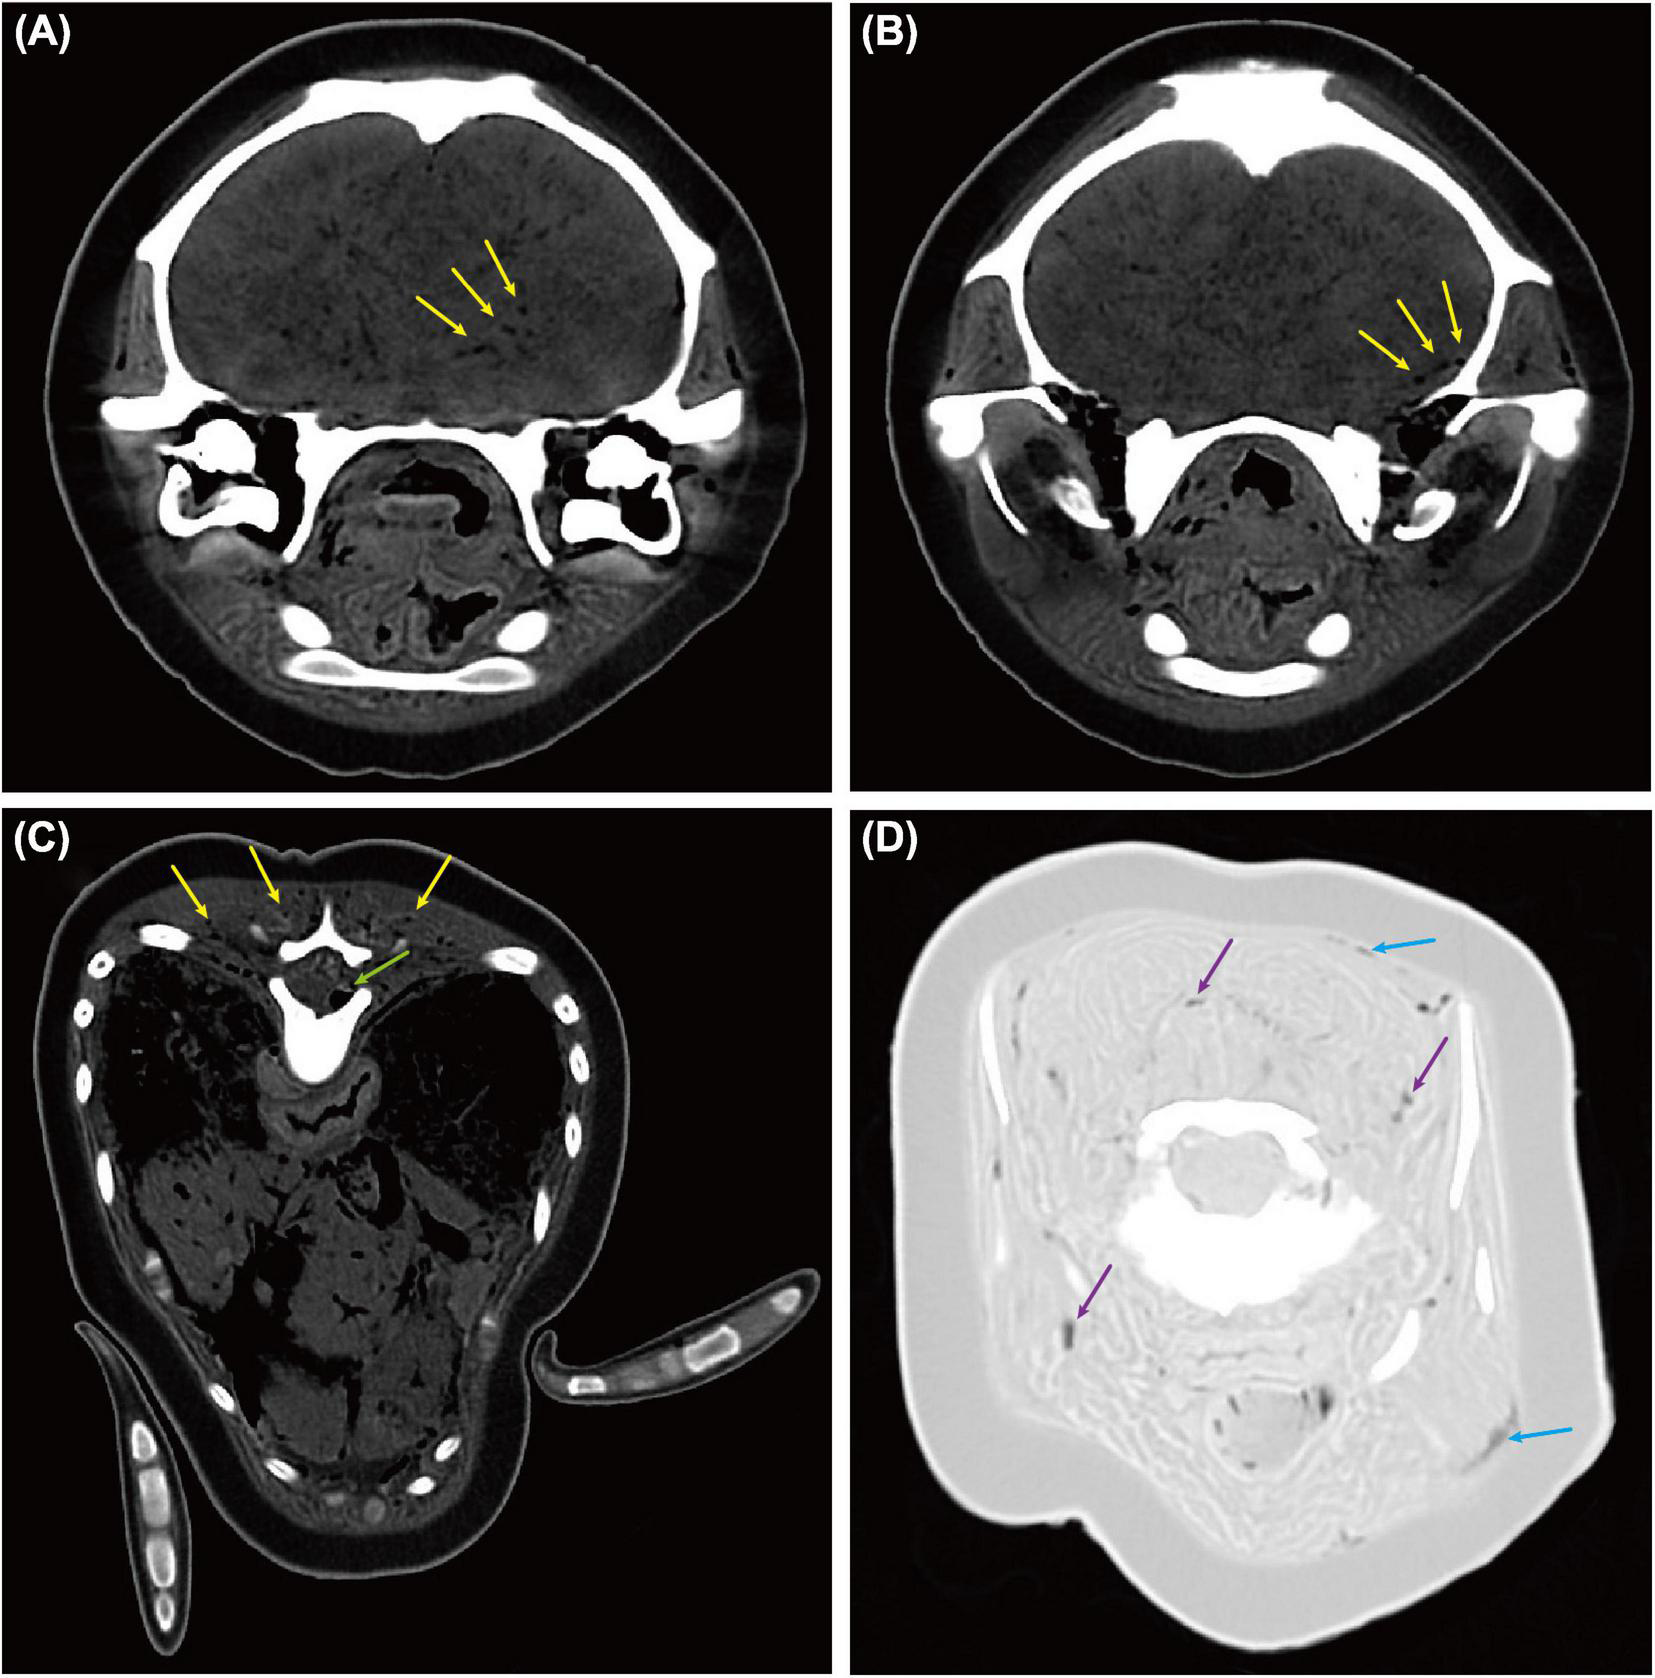

Gas bubbles ranging from 0.7 to 3.0 mm in diameter were also found from brain tissue (Figures 5A,B) (WL/WW: 152/524 HU), spinal cord (Figure 5C) (WL/WW: 152/524 HU), epaxial and cervical muscles (Figures 5C,D), and sub-dermal tissue (Figure 5D) (WL/WW: −500/1,400 HU) using PMCT. However, gas bubbles were too small to be visible during necropsy. Therefore, they were not able to locate for histopathological investigation.

FIGURE 5

Computed tomographic (CT) findings in the brain, spinal cord, muscles, and sub-dermal tissue of an East Asian finless porpoise (Neophocaena asiaeorientalis sunameri) carcass. Gas bubbles ranging from 0.7 to 3.0 mm in diameter were found through various tissues. (A,B) Transverse CT images (WL/WW: 152/524 HU) showing gas bubbles (yellow arrows) in brain tissue. (C) Transverse CT image (WL/WW: 152/524 HU) showing gas bubbles in epaxial muscles (yellow arrows) and spinal cord (green arrow). (D) Transverse CT image (WL/WW: –500/1,400 HU) showing gas bubbles in sub-dermal tissue (blue arrows) and cervical muscles (purple arrows).